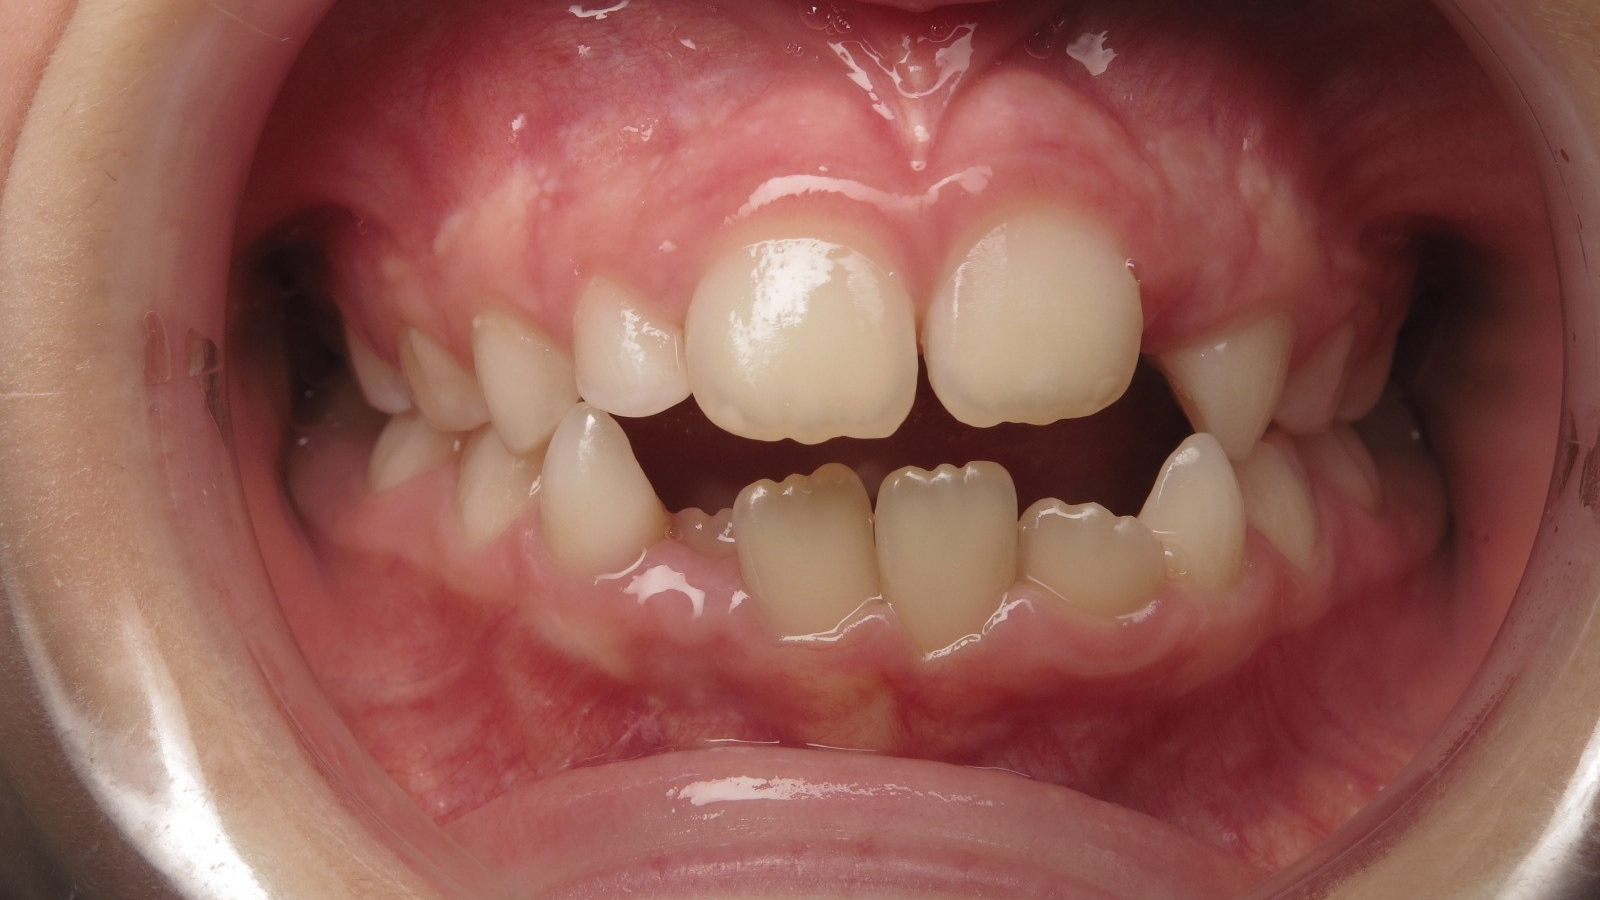

14 béance inversé gauche 5 ans

sectionnel multibagues pendant 8 mois

surveillance évolution de la dentition en cours

bilan début et en cours de traitement